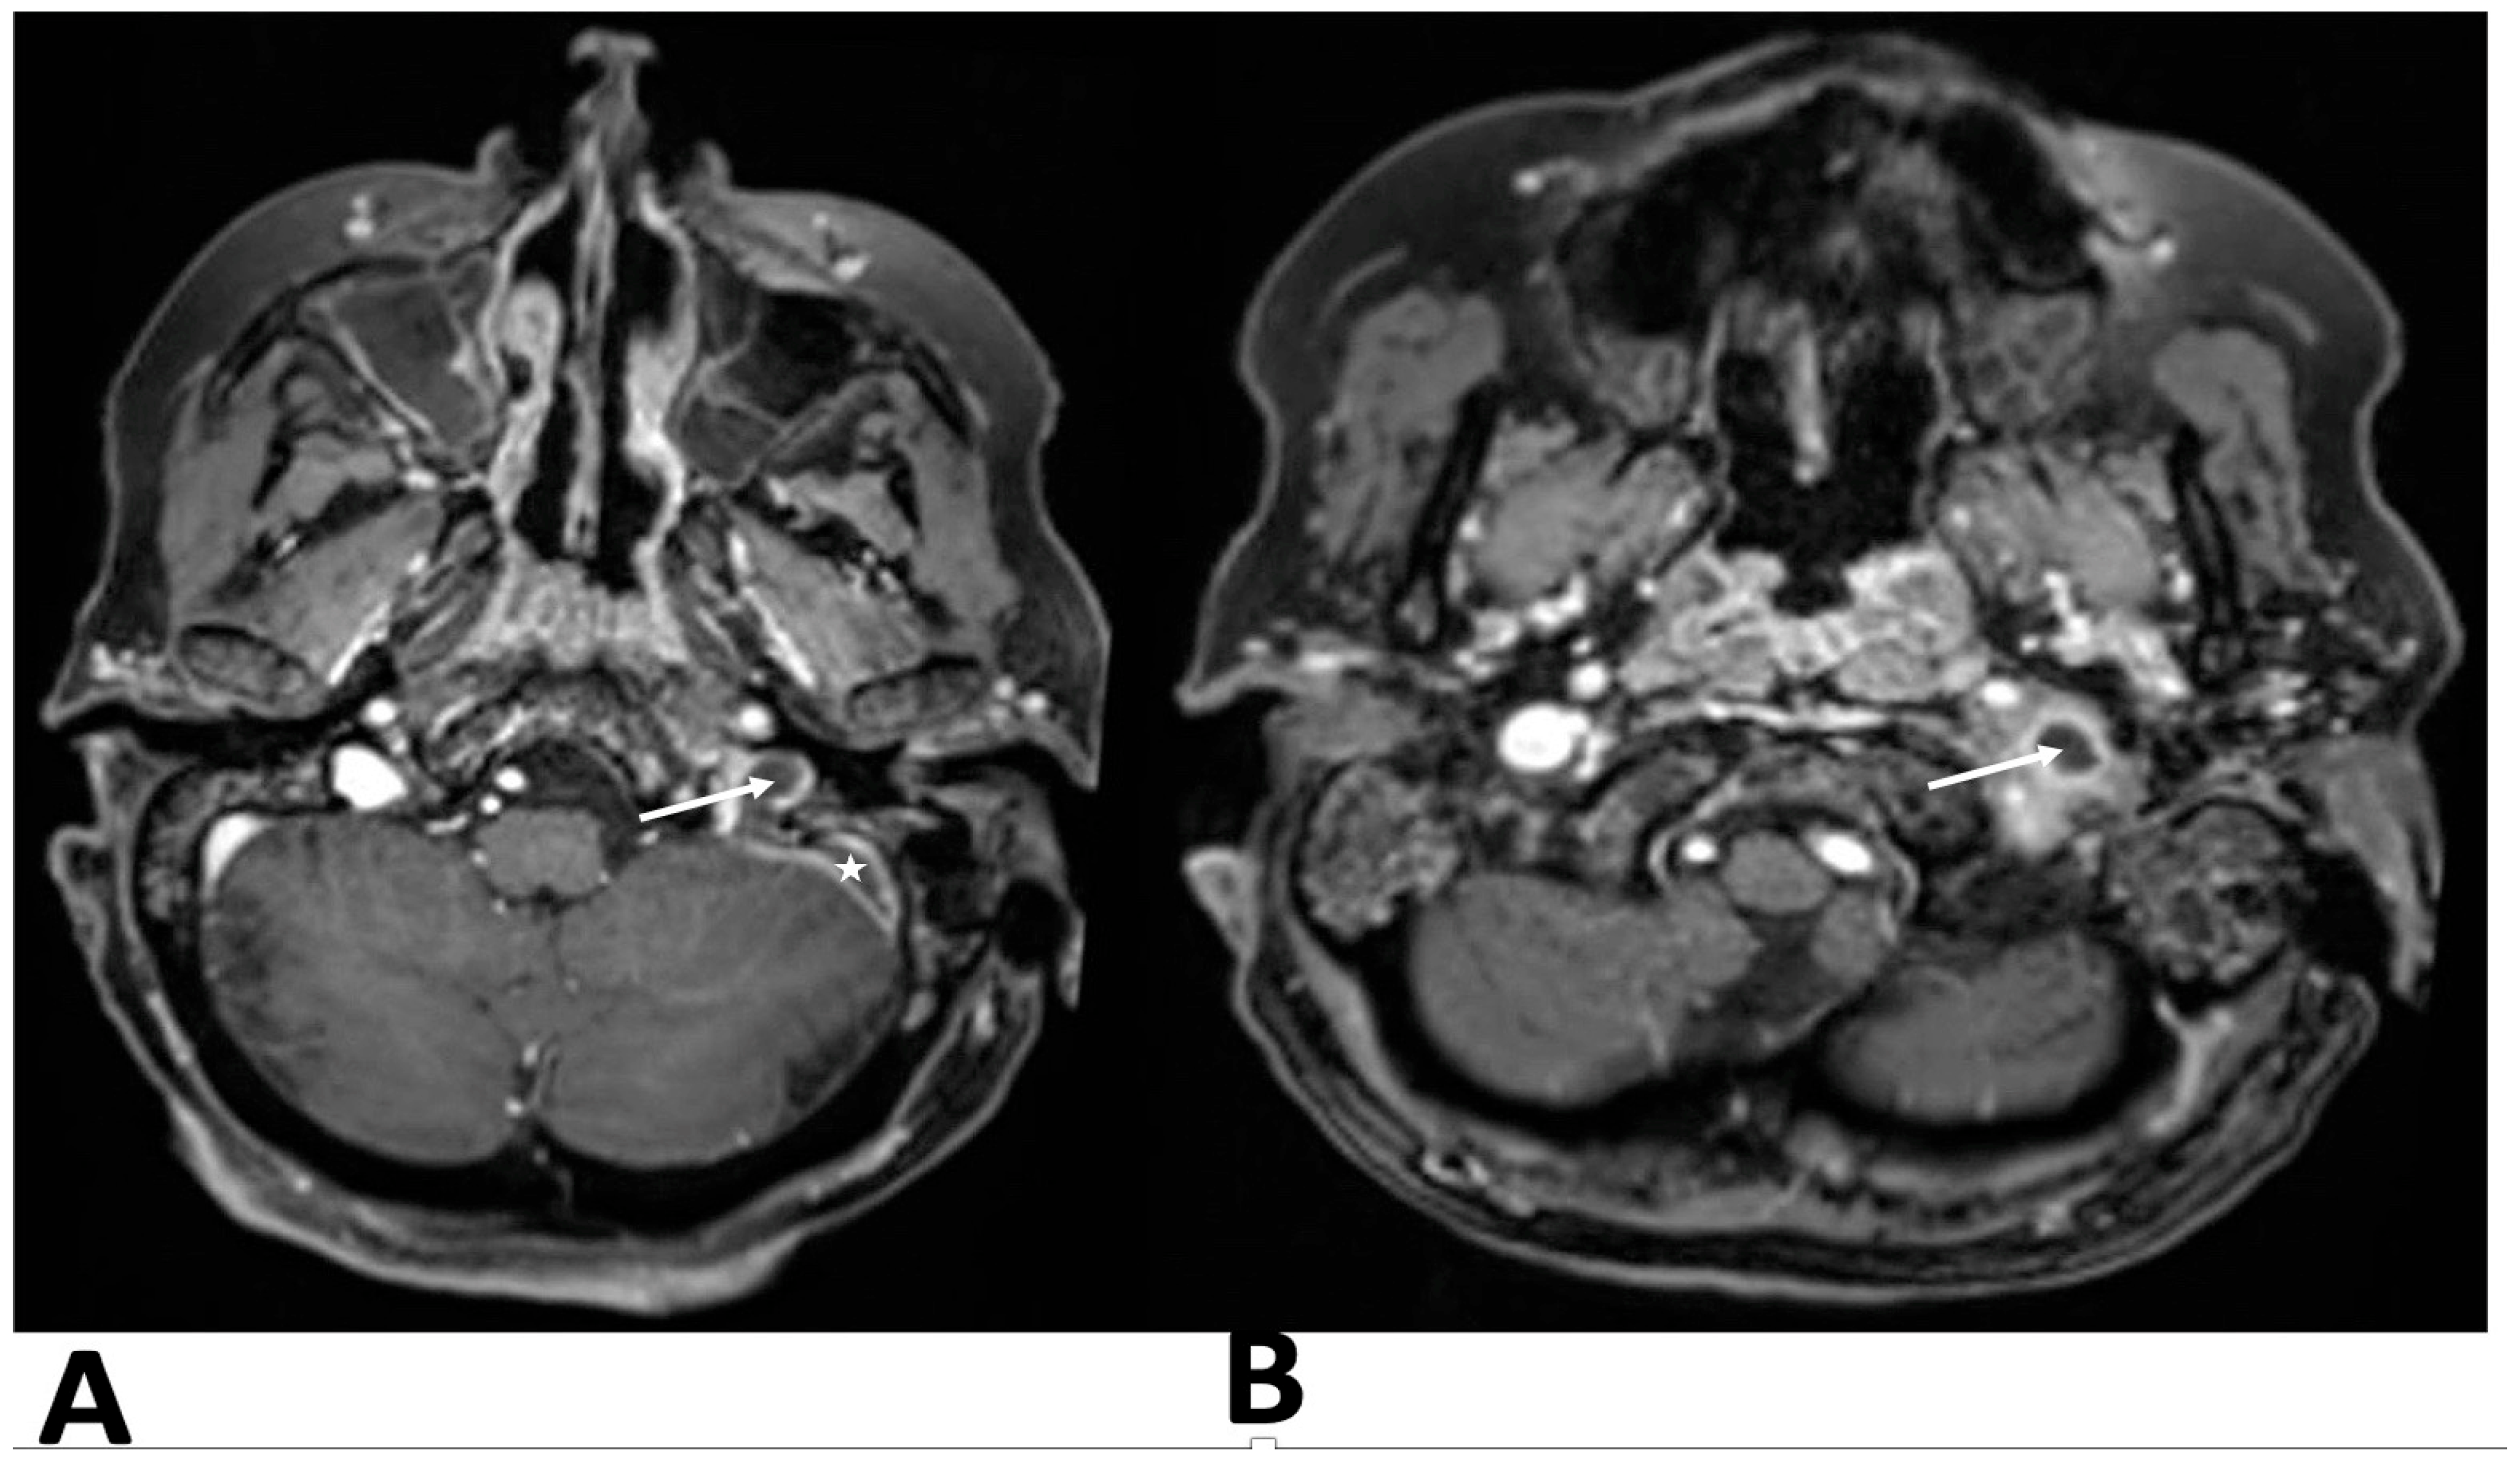

After contrast administration, the left jugular bulb and sigmoid sinus were not opacified, suggesting acute thrombosis at the proximal end of the jugular vein and sigmoid sinus. Brain and skull base magnetic resonance imaging (MRI) and magnetic resonance venography (MRV) confirmed temporal bone inflammation, sigmoid sinus thrombosis extending to the internal jugular vein, jugular vein thrombophlebitis, and no other intracranial complications (

Figure 2).

In such cases, contrast-enhanced computed tomography (CT) is the primary diagnostic modality. Although magnetic resonance venography (MRV) is not crucial for diagnosing vein thrombosis, it helps determine the extent of the thrombotic process and monitor the progress of anticoagulation therapy. Additionally, magnetic resonance imaging (MRI) scans were performed on patients showing clinical symptoms or CT findings suggestive of intracranial complications, as the MRI has proven to be more sensitive in detecting these issues.